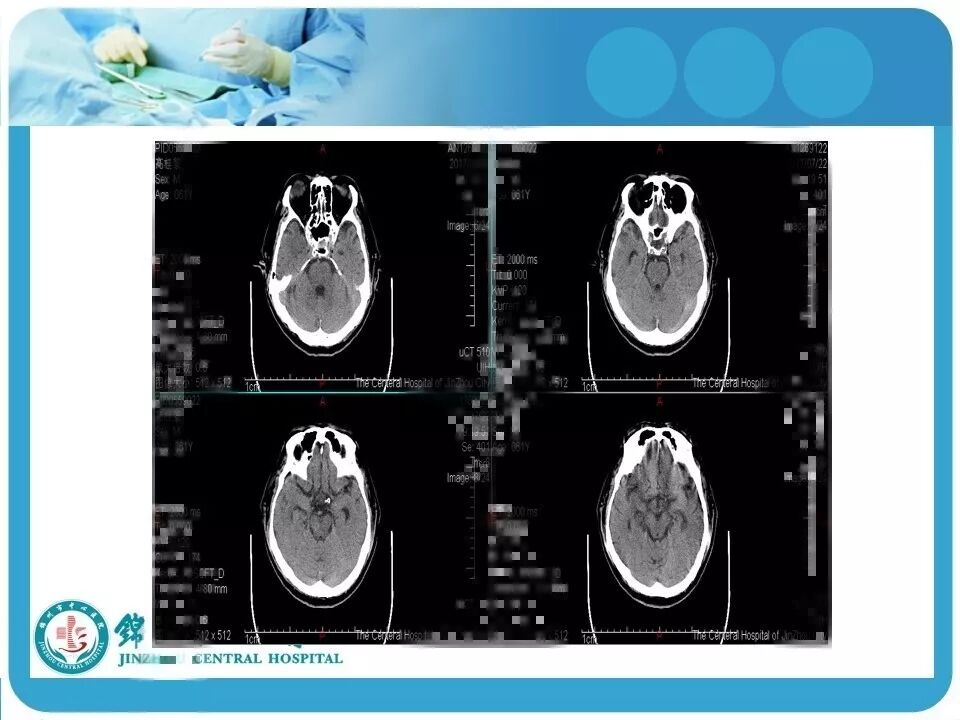

2. 弥漫性轴索损伤(DAI)的影像学诊断。单纯CT图像不能直接显示脑内白质纤维的损伤,如情况容许,行MRI检查(DWI或DTI成像)对病情的评估更有帮助,可能患者的损伤远比CT上几个出血点严重;